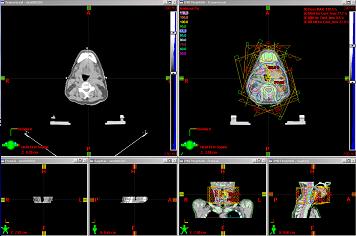

Srovnání plánů

Rovina izocentra

Povrtal vision